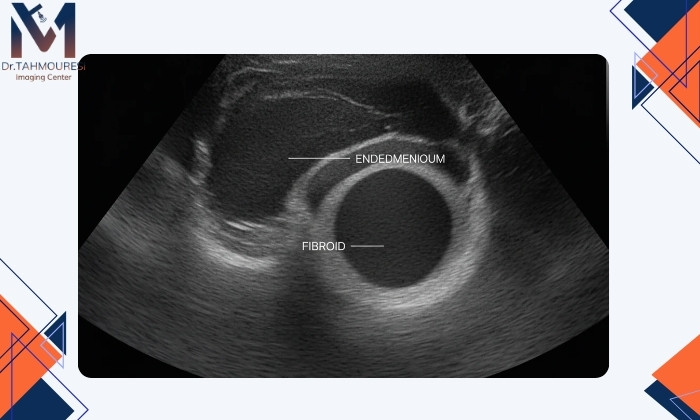

تشخیص فیبروم رحم با سونوگرافی

نقش اولتراسوند در تشخیص فیبروم رحم

اولتراسوند بهویژه نوع ترانس واژینال قادر است اندازه، محل و تعداد فیبرومها را با دقت بالا نشان دهد.در حدود ۸۰ تا ۹۰ درصد موارد میتواند فیبرومهای متوسط و بزرگ را بهدرستی شناسایی کند.